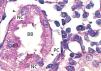

The proximal tubules’ structure in the negative control group was normal (Figure 1). Significant damage was observed to the kidneys from the positive control and oxygen groups (loss of brush border, tubular dilation, epithelial cell necrosis, formation of cylinders in the tubular lumen, interruption and/or effacement of the TBM) (Figures 2 and 3).

Ozone postconditioning caused recovery of tubular morphology. The proximal tubules’ brush border and other cell structures were better preserved (Figure 4). The animals from the ozone group showed significantly less overall histological damage than the positive control and oxygen groups (Figure 5).

Figure 1. Negative control animal¿s proximal tubule in the medullary and cortical regions. PAS staining

Figure 2. Positive control animal¿s proximal tubule in the medullary and cortical regions. PAS staining

Figure 3. Ozone-treated animal¿s proximal tubule in the medullary and cortical regions. PAS staining

Figure 4. Oxygen-treated animal¿s proximal tubule segments in the medullary and cortical regions. PAS staining